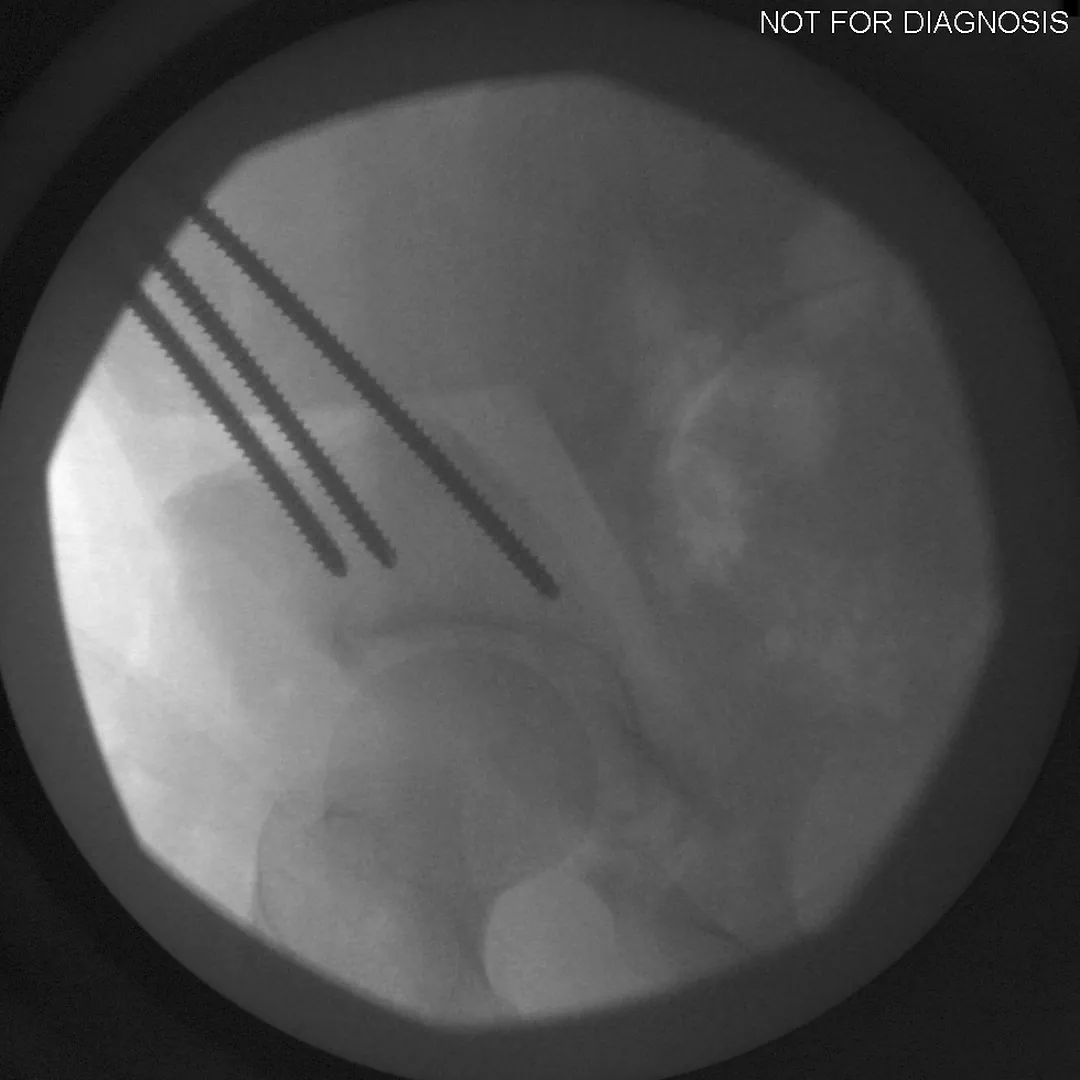

During a PAO, the surgeon carefully cuts the bone around the hip socket and repositions it to provide better coverage of the femoral head. The socket is then fixed in its new position using screws. The goal is to improve hip stability, reduce pain, and preserve the patient’s natural hip joint.

• Several controlled bone cuts are made around the hip socket

• The socket is repositioned and fixed with screws